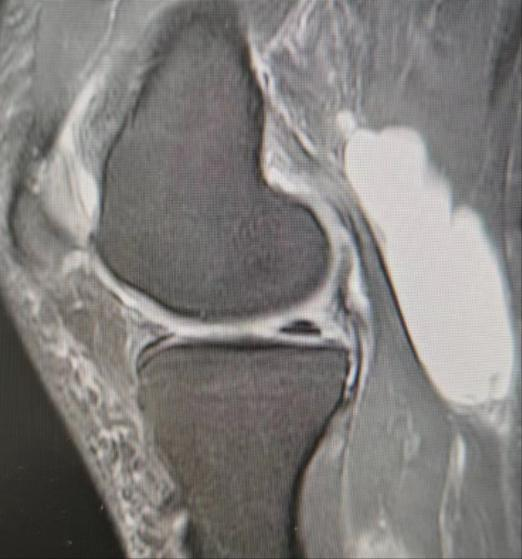

病例1,患者左膝关节疼痛不适半年,行经查体及MRI检查诊断为:左膝内侧半月板损伤、腘窝囊肿、骨性关节炎,给予行“左膝关节镜下内侧半月板、软骨修整成形及腘窝囊肿切除术”。

病例2,患者左膝关节疼痛不适2月,经查体及MRI检查诊断为:左膝内外侧半月板损伤、腘窝囊肿、骨性关节炎,考虑囊肿较小,且为单房囊肿,行“膝关节镜下半月板、软骨修整成形术”的同时,给予切除“活瓣”,行“腘窝囊肿减压术”。

腘窝囊肿又叫“Baker囊肿”,分为原发性和继发性两种,前者儿童多见,后者中老年多见,绝大多数的腘窝囊肿继发于膝关节内病损,包括半月板损伤、骨关节炎、类风湿关节炎、色素沉着绒毛结节性滑膜炎等。发病原理是单向流通的“活瓣”(只进不出),即腘窝囊肿通道口存在的皱襞、束带或关节内疾患堵塞通道口,增多的关节积液可通过通道进入滑囊,但不能从滑囊回到关节腔,导致囊肿的形成和持续存在。目前膝关节镜下腘窝囊肿切除术已成为主流手术方式,关节镜下不仅能切除囊肿,还能处理半月板损伤、骨关节炎等关节内疾病,大大降低了复发的几率。